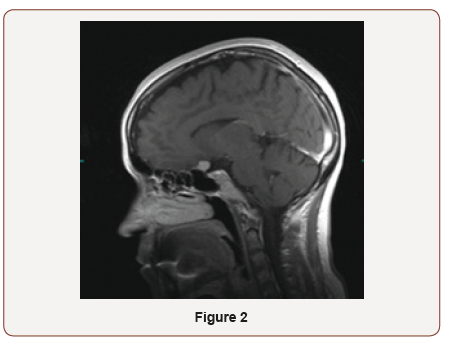

The patient is a 39-year-old female who was referred to neuroophthalmology office on November 2018 for the optic atrophy of left eye. She had noticed vision less in the left eye when she went to DMV for renewal of her license. She was not aware of the duration of vision loss. There was no history of pain with eye movement, trauma to the eye, infectious, and or inflammatory disease. She denied headaches, diplopia, numbness or tingling, and low back pain. Her past medical and surgery history was not significant. In eye exam, her vision was 20/25 on right and 20/150 left eye. Color vision was 11/11 in right and 1/11 in left eye. She had RAPD in left eye. Visual field of the right eye was normal. She was not able to do visual field on the left side. OCT optic nerve showed mild RNFL thinning on the left eye. MRI brain and orbit showed an enhancing mass impressing on the posterior aspect of the left optic nerve showing a slight dural tail measuring 13.1x11.1x12.2 mm, consistent with meningioma. The mass encases left internal artery. She was referred to neurosurgeon for tumor resection. She gained back some of her vision immediately after surgery. The patient came back for follow up on December 2018. Her vision was 20/20 in both eyes and color vision on left eye was improved to 5/11 (Figure 1,2).